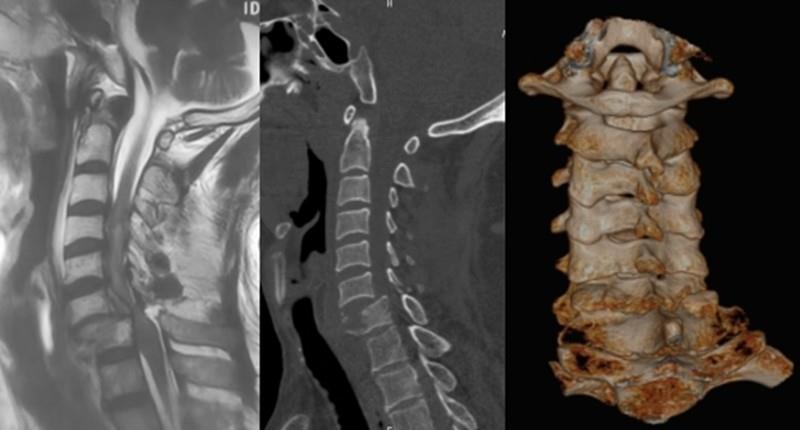

近日,漯河市中心医院骨科团队完成了一例针对严重颈椎外伤患者的急诊微创手术。一名壮年男性因外伤导致颈6/7椎体骨折脱位,右侧关节突绞索,脊髓严重受压,出现四肢瘫痪症状,情况危急。面对这一复杂伤情,团队果断采用了一项原创性的“先减压后复位”理念及“单侧偏心撑开、后凸撑开撬拨复位”技术,在50分钟内成功完成了脱位复位、脊髓减压与内固定,术中出血量控制在约30毫升。

此次手术在国务院特殊津贴专家、骨科主任医师李玉伟教授带领下实施。手术摒弃了常规的牵引等待环节,直接进入手术室。团队通过单纯的前路切口,先切除了导致脊髓压迫的突出椎间盘及骨折碎片,实现了脊髓的即时减压,为后续操作创造了安全空间。紧接着,团队运用“单侧偏心撑开”联合后凸撑开撬拨技术,成功完成了脱位关节的复位。